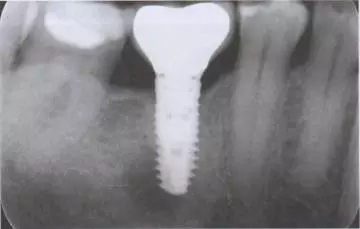

圖1 患者46牙根管再治療失敗,出現(xiàn)根尖炎癥,準(zhǔn)備拔除做即刻種植

圖2 小視野CBCT圖像顯示種植修復(fù)一年后的骨容解情況